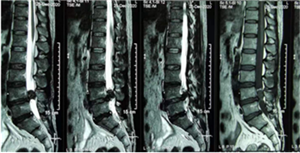

腰椎MRI示L4/5巨大腰椎间盘突出伴椎管狭窄